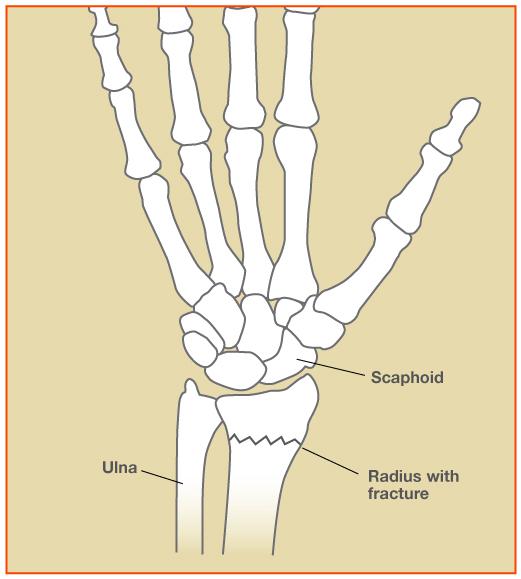

Types Of Wrist Fractures – Fracture Treatment

What is Closed Fracture of the Wrist, Know its Treatment, Recovery …

Wrist Fractures (Distal Radius Fractures) – Pro doctor

Wrist Fractures (Distal Radius) – Hobart Orthopaedics

What Is A Wrist Fracture?

Colles’ Fractures (Broken Wrist) | Florida Orthopaedic Institute

Distal radius fracture: causes, symptoms, conservative and surgical …